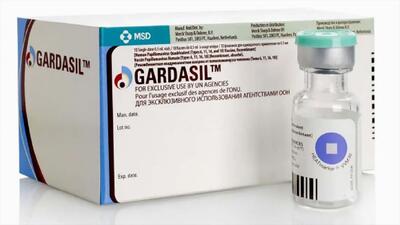

زگیل تناسلی و همه چیز در مورد این زائده های ناحیه تناسلی و درمان آن

زگیل تناسلی یکی از شایع ترین عفونت های ویروسی منتقله از راه جنسی است که توسط ویروس پاپیلومای انسانی ایجاد می شود. این عارضه معمولاً به صورت زائده های کوچک،

محققان در بررسیهای جدید خود به شواهدی دست یافتهاند که نشان میدهد پیشگیری و درمان عفونتها، شامل استفاده از واکسنها، آنتیبیوتیکها و داروهای ضد ویروسی، میتواند نقش مهمی در جلوگیری از زوال عقل ایفا کند. این یافتهها از ایده ارتباط میان عفونتها و خطر زوال عقل حمایت میکند.